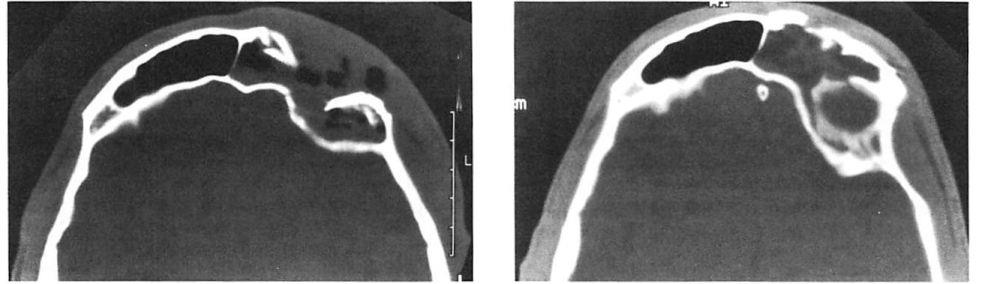

Fig 4. Highly comminuted fracture of supraorbital portion of large frontal sinus that extends to lateral orbit treated with open reduction and microplate and screw fixation. (A) Preoperative axial computed tomographic (CT) scan. (B) Postoperative axial CT shows stable reduction 2 months after injury. Note symmetrical contour of frontal soft tissues.

Fig 4. Highly comminuted fracture of supraorbital portion of large frontal sinus that extends to lateral orbit treated with open reduction and microplate and screw fixation. (A) Preoperative axial computed tomographic (CT) scan. (B) Postoperative axial CT shows stable reduction 2 months after injury. Note symmetrical contour of frontal soft tissues.